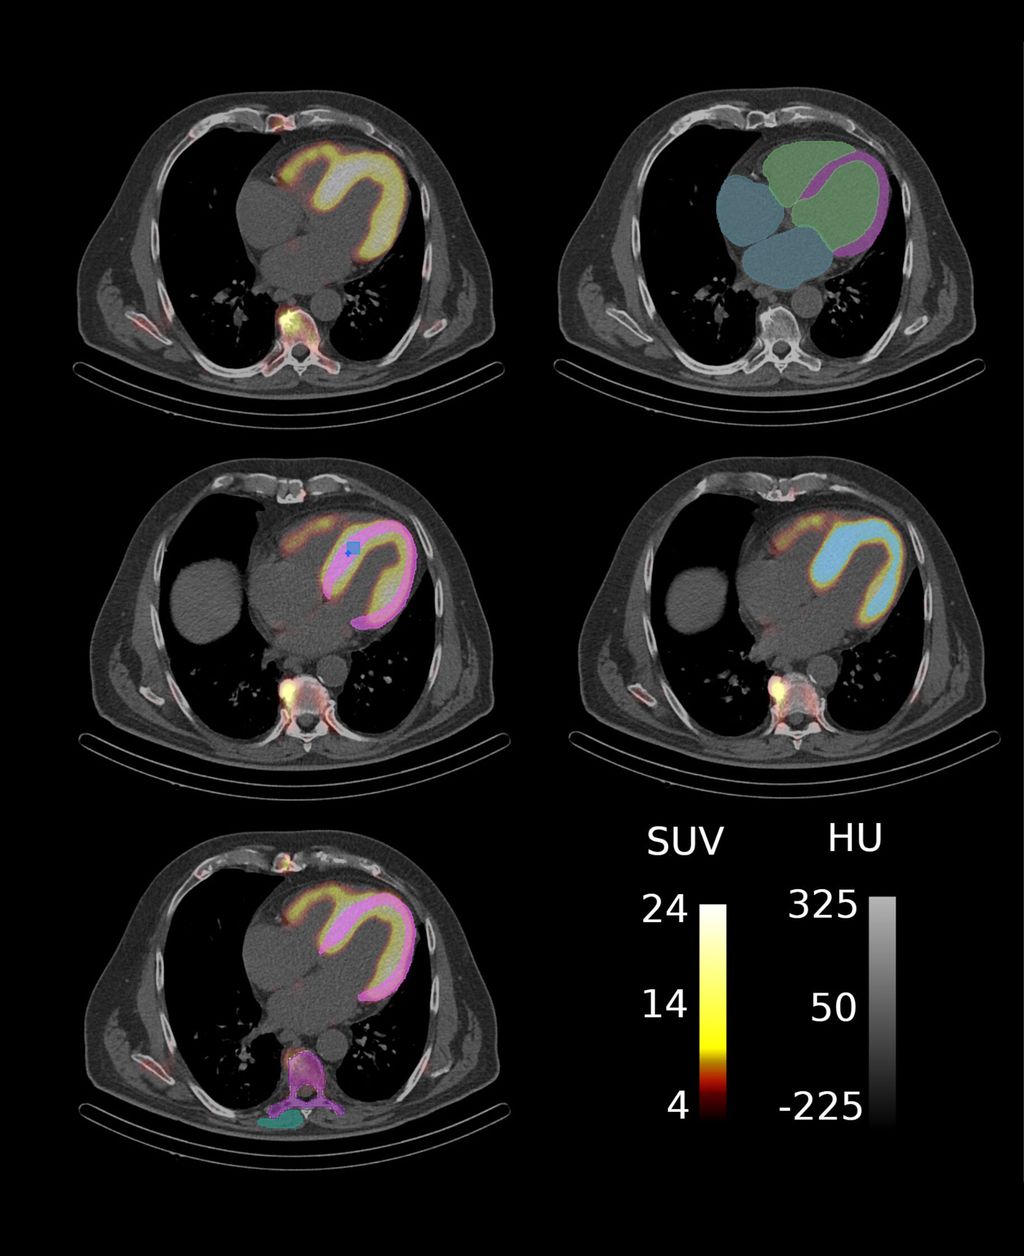

Im Rahmen einer explorativen bildgebenden Studie der Klinischen Abteilung für Kardiologie in Kooperation mit der Klinischen Abteilung für Nuklearmedizin der Medizinischen Universität Wien wurde der Einfluss amyloidspezifischer Therapien auf SPECT/CT-basierte Marker untersucht (Abb. 2), die myokardiale Amyloidablagerungen widerspiegeln. Die KI-gestützte Segmentierung der kardialen Strukturen ermöglicht eine umfassende Quantifizierung der Amyloidablagerungen im Myokard und können als potenzielle nichtinvasive bildgebende Biomarker zur Überwachung der therapeutischen Wirksamkeit bei Patient:innen mit ATTR-CM dienen (Abb. 3).

Die Studienkohorte umfasste 45 Patient:innen mit ATTR-CM, die eine amyloidspezifische Therapie, wie TTR-Stabilisatoren (Tafamidis) oder TTR-Silencer (Patisiran, Inotersen), erhielten und sich sowohl vor Therapiebeginn als auch nach neun Monaten im Rahmen eines Follow-ups einer SPECT/CT-Bildgebung unterzogen. Die KI-gestützte Segmentierung der kardialen Strukturen erfolgte mithilfe eines Deep-Learning-Modells, das die automatisierte Extraktion von 23 quantitativen Markern ermöglichte, darunter Intensitäts- und Volumenmarker des Tracer-Uptakes sowie der Retentionsindex über verschiedene kardiale Substrukturen. Darüber hinaus wurden funktionelle Parameter – einschließlich klinischer und laborchemischer Variablen – sowie klinische Endpunkte hinsichtlich ihrer Assoziation mit Veränderungen der SPECT/CT-Marker vor und nach der Behandlung untersucht.

Abb. 2: ATTR-CM Patient mit Segmentierungsmasken für myokardbasierte Marker: (a) SPECT/CT Aufnahme, (b) CT-Aufnahme mit Basis-Segmentierungen, (c) Segmentierung zur Extraktion klassischer SUV-Parameter wobei SUVpeak in Hellblau und SUVmax in Dunkelblau dargestellt ist, (d) Segmentierung des Amyloid-assoziierten Volumens und (e) Segmentierungen für den Retentionsindex. (Quelle: eigene Anfertigung)

Im Therapieverlauf zeigten sich signifikante Reduktionen bei 14 von 16 (88%) SPECT/CT-Markern, insbesondere eine deutliche Abnahme der Tracer-Aufnahme im linken Ventrikel und Myokard. Diese Veränderungen korrespondierten mit Verbesserungen funktioneller Parameter. So war ein reduzierter NT-proBNP-Wert mit einer geringeren Tracer-Aufnahme assoziiert, insbesondere in Bezug auf den SUVpeak-Wert des Myokards und den SUVmax-Wert des Myokards, des rechten und des linken Ventrikels. Darüber hinaus ging eine Reduktion des Retentionsindex mit einer Verbesserung der „New York Heart Association (NYHA)“-Klasse einher. Angaben zu herzinsuffizienzbedingten Hospitalisierungen (HFH) lagen für 30 von 45 (67%) Patient:innen vor, von denen 9/30 (30%) ein Ereignis nach einem medianen Follow-up von 34,9 Monaten aufwiesen.

Die Studie unterstreicht den Nutzen der KI-gestützten SPECT/CT-Bildgebung zur Erfassung therapieinduzierter Veränderungen der kardialen Amyloidlast bei Patient:innen mit ATTR-CM. Die automatisierte Markerextraktion durch KI reduziert die Variabilität zwischen Auswerter:innen, erhöht die Effizienz und verbessert die Reproduzierbarkeit. Die Ergebnisse verdeutlichen das Potenzial von SPECT/CT-Markern als sensitive, nichtinvasive Bildgebungsbiomarker zur frühen Beurteilung des Therapieansprechens und bieten damit eine Alternative zur kardialen Magnetresonanztomografie bei ATTR-CM-Patient:innen mit implantiertem Schrittmacher oder Defibrillator. Diese Erkenntnisse ebnen den Weg für personalisierte Behandlungsstrategien und eine breitere klinische Anwendung von KI in der Nuklearmedizin.